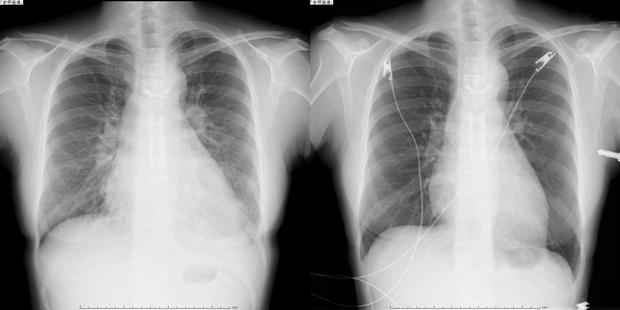

以下に当院に心不全入院してTAVIを受けることでレントゲンを含めて病状がが改善した症例を示します。

Evolut R植込み術

レントゲン写真(左:治療前、右:治療後)